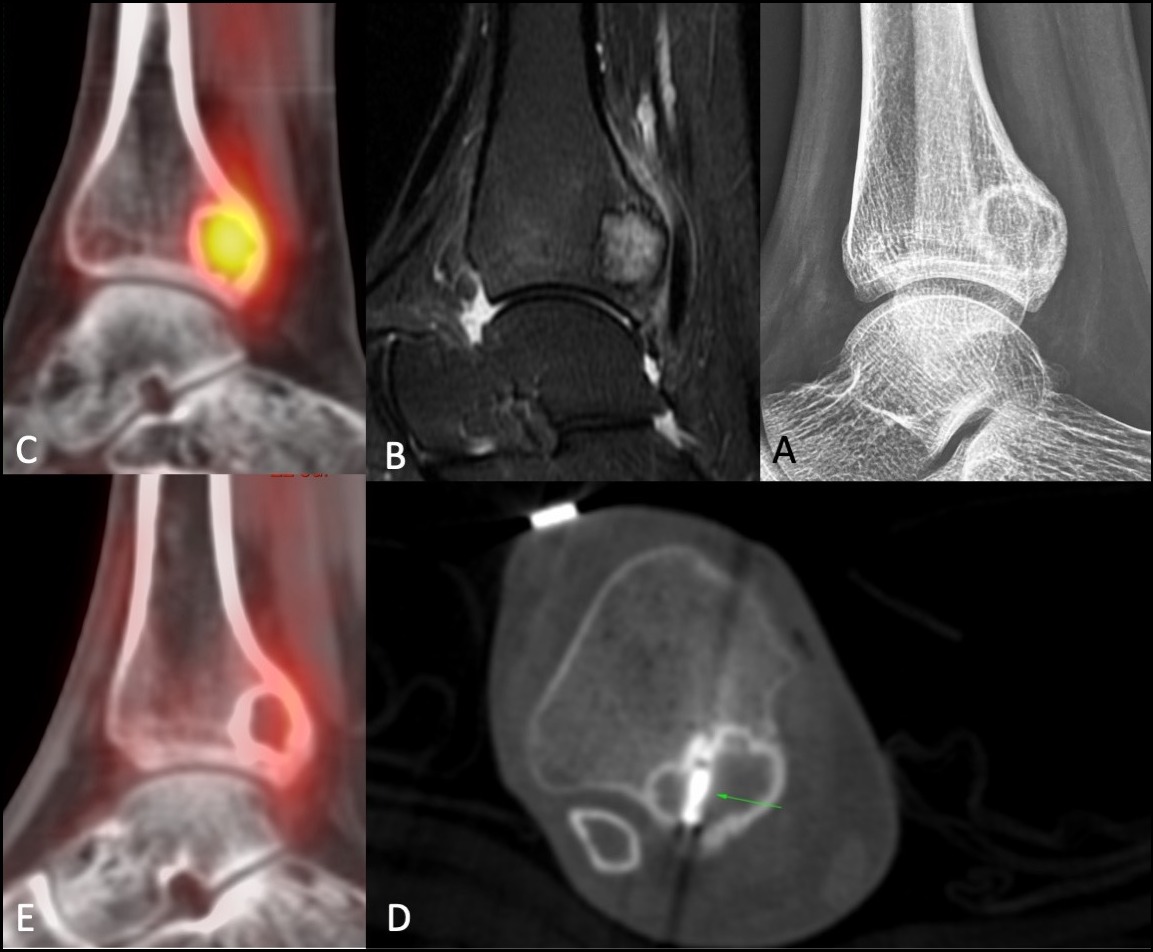

At Picture This Imaging, we prioritise patient wellbeing through cutting-edge, minimally invasive procedures that deliver targeted results and shorter recovery times. Our expert-led radiology team uses advanced image guidance to treat rare bone tumours with confidence and care. We offer cryoablation for osteoblastoma, a specialised approach that involves freezing the tumour with extreme precision, preserving surrounding tissue and reducing the need for open surgery. This outpatient procedure is often favoured for its safety, reduced discomfort, and faster return to normal activity. Each case is handled individually with a thorough assessment, expert supervision, and comprehensive follow-up. At Picture This Imaging, we ensure every patient receives trusted, evidence-based treatment in a supportive and modern environment.